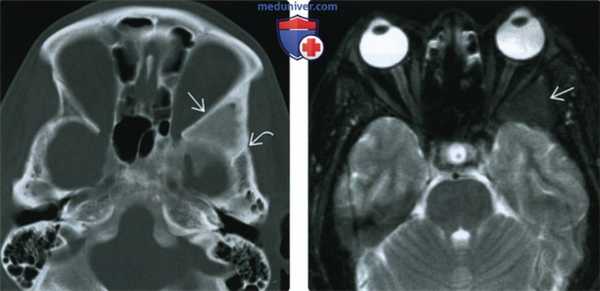

(Слева) При аксиальной КТ в костном окне определяется фиброзная дисплазия (ФД) склеротического типа, с поражением сосцевидного отростка и внутреннего уха и обрастанием задних отделов среднего уха. Экспансивный характер ФД приводит к стенозу наружного слухового канала (НСК). Обратите внимание на область ранее выполненной биопсии спереди и снаружи.

(Справа) При корональной КТ в костном окне определяется склеротическая ФД, приводящая к окклюзии НСК. Можно предположить наличие клинически значимой кондуктивной тугоухости. При отоскопии определяются изменения, схожие с врожденной мальформацией ИСК.2. КТ при фиброзной дисплазии височной кости:

(Слева) При аксиальной КТ в передних отделах левой височной кости определяются очаги кистозной ФД, выглядящие агрессивными. Определяется также нежное «матовое стекло». Обратите внимание на визуализирующийся лабиринтный сегмент канала лицевого нерва и поражение ямки коленчатого ганглия.

(Справа) При аксиальной КТ в костном окне определяется полиостотическая фиброзная дисплазия с поражением обеих височных костей. Хорошо видны другие множеавенные очаги, в т.ч. в затылочной кости справа, в скате, клиновидной и лобной кости.в) Дифференциальная диагностика фиброзной дисплазии височной кости: